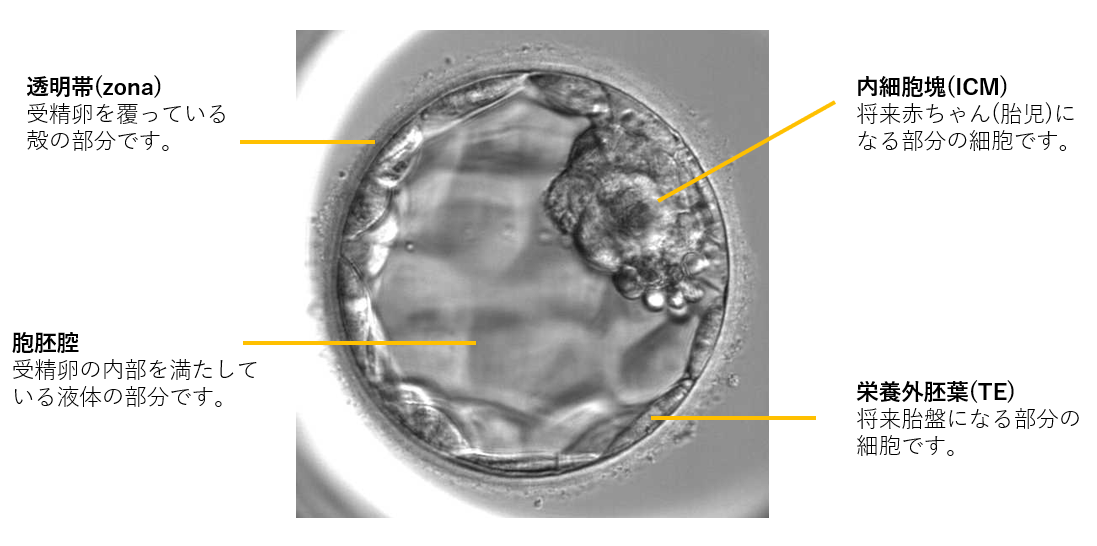

胚盤胞の特徴

胚盤胞になると、分割胚とは明らかに違い、胚には将来赤ちゃんになる内部細胞塊と将来胎盤になる栄養外胚葉があり、より生命の発生に近づいた構造を見せるようになります。評価はこれらの細胞を胚培養士が見た目での形態観察でおこない判定しています。

胚盤胞の様子

受精後5~6日目

受精後5~6日目の胚盤胞を対象に、胚盤胞がどれだけ成長して膨らんでいるかをみる拡張度ステージ、将来的に胎児となる部分の細胞の数や密度をみる内細胞塊ICM評価、将来的に胎盤となる部分の細胞=栄養外胚葉TEの状態、この3つの要素(数字と2つのアルファベット)で評価判定します。

<評価は内部細胞塊と栄養外胚葉の発育をそれぞれ3段階でおこなう>

内細胞塊(ICM)の評価:

将来的に胎児となる部分の細胞の数や密度を評価

栄養外胚葉(TE)の評価:

将来、胎盤となる部分の細胞の状態を評価